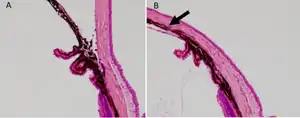

| b) Anterior segment of laser-treated a) and control eye was histologically assessed. The arrow indicates the closed angle induced by laser photocoagulation. | |